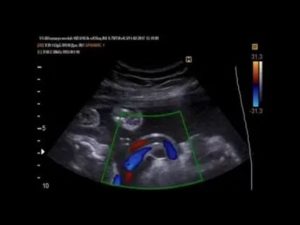

- Допплерометрия, которая заключается в проведении исследования кровотока пуповины;

Обвитие можно обнаружить с помощью

с пятнадцатой недели вынашивания. Для того чтобы определить насколько сильно тельце малыша сдавливается, делается допплерометрия. В том случае, если существует вероятность кислородного голодания, обследование проводится не один раз.